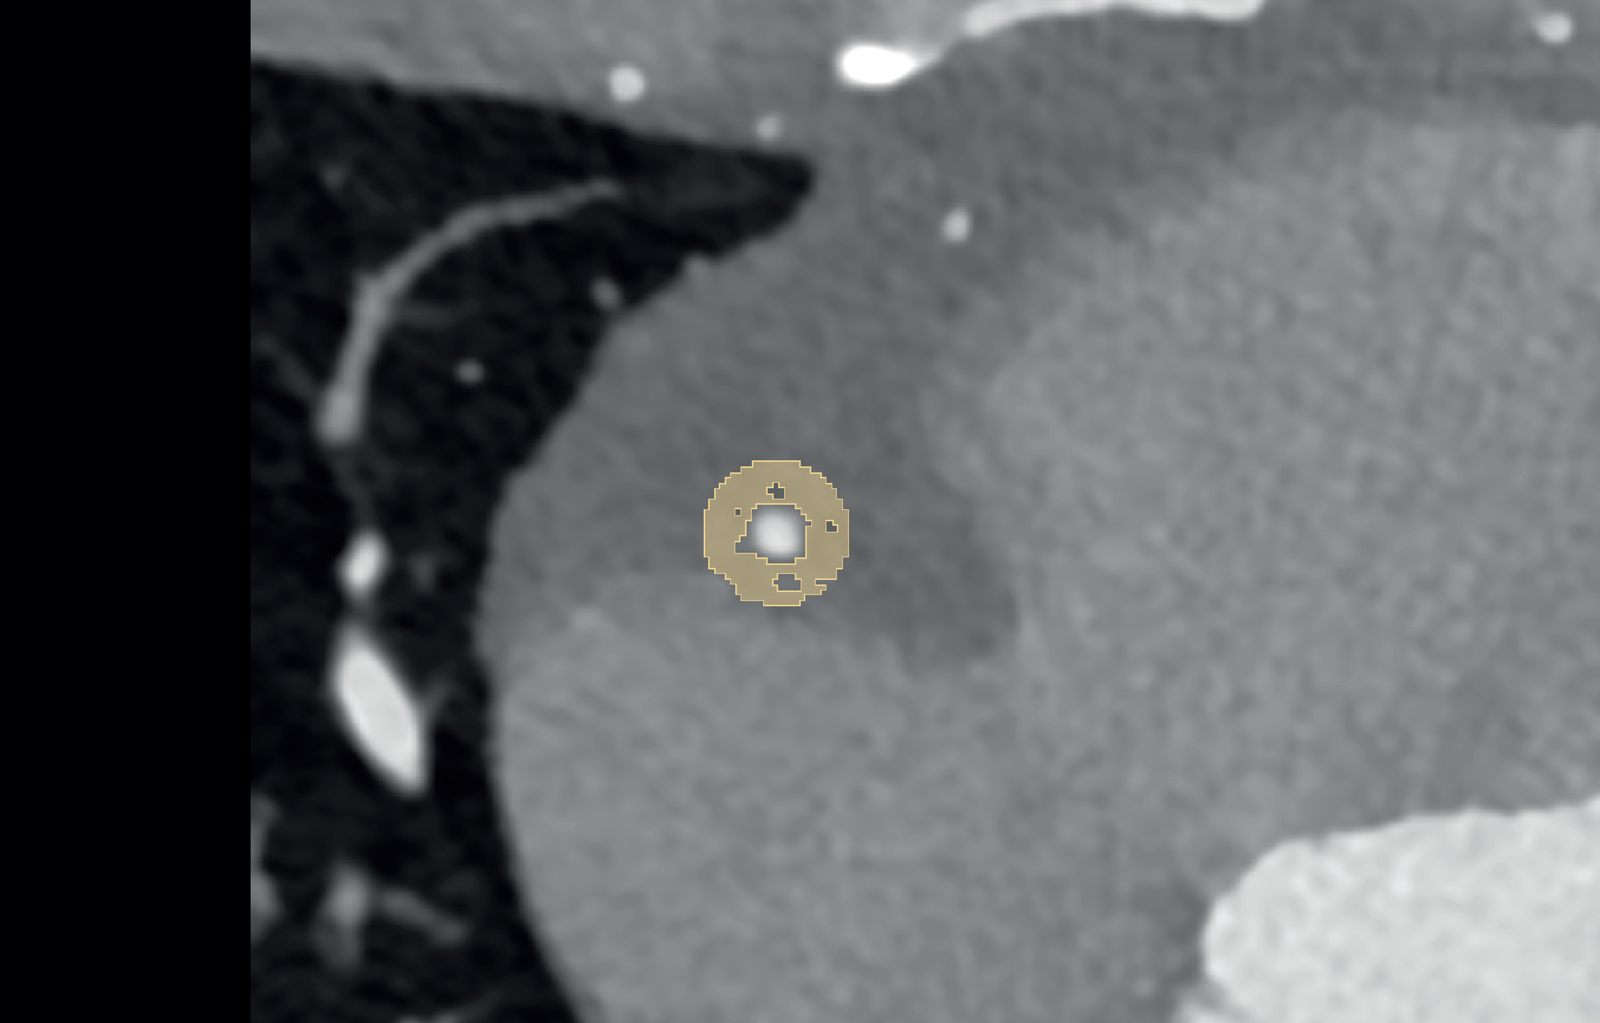

Estimation of coronary artery calcification was performed on axial non-enhanced scans with 3 mm slice thickness and Qr36 kernel using dedicated software (syngo.via, Siemens Healthcare GmbH, Forchheim, Germany). Axial images of contrast-enhanced CCTA were reconstructed using a slice thickness of 0.6 mm, an increment of 0.4 mm, and a soft vascular kernel (Bv40). These images were anonymized, exported, and stored in Digital Imaging and Communications in Medicine (DICOM) file format. Afterward, they were converted into Neuroimaging Informatics Technology Initiative (NIFTI) file format and uploaded into a dedicated segmentation tool (3D Slicer, Version 4.11) (21). The pericoronary adipose tissue was segmented manually by a medical student with one year of experience in segmentation and validated by a senior radiologist with ten years of experience in cardiothoracic imaging and six years of experience in segmentation. Pericoronary adipose tissue was defined as any voxel between −30 and −190 Hounsfield units (HU) surrounding the right coronary artery (RCA) or left anterior descending artery (LAD) along 6 cm starting 1 cm after the ostium of the RCA and along 4 cm directly after the bifurcation of the left main artery (LM). The segmentation was performed within a radial distance from the outer vessel wall equal to the diameter of the underlying vessel. Depending on the vessel, this radial distance was between 2 mm and 6 mm. Figure 1 shows an example segmentation of the pericoronary adipose tissue in an axial view.

Figure 1

Example segmentation of pericoronary adipose tissue (in yellow) in a 39-year-old male on axial reconstructed images.